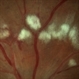

- A 73-year-old woman with macular pucker underwent a pars plana vitrectomy with membrane peeling. Additionally the patient suffers from diabetic retinopathy after being diagnosed with type 2 diabetes mellitus sixteen years ago. Prior to the procedure she was treated with a series of intravitreal Bevacizumab-injections due to diabetic macular edema. There was no history of a proliferative DRP. During the vitrectomy a branch of an obliterated NVE spontaneously detached and floated freely in the vitreous. The 3D shot was captured via Alcon’s NGENUITY® 3D Visualization System in form of photograph and video providing an outstandingly detailed image of the branched NVE.